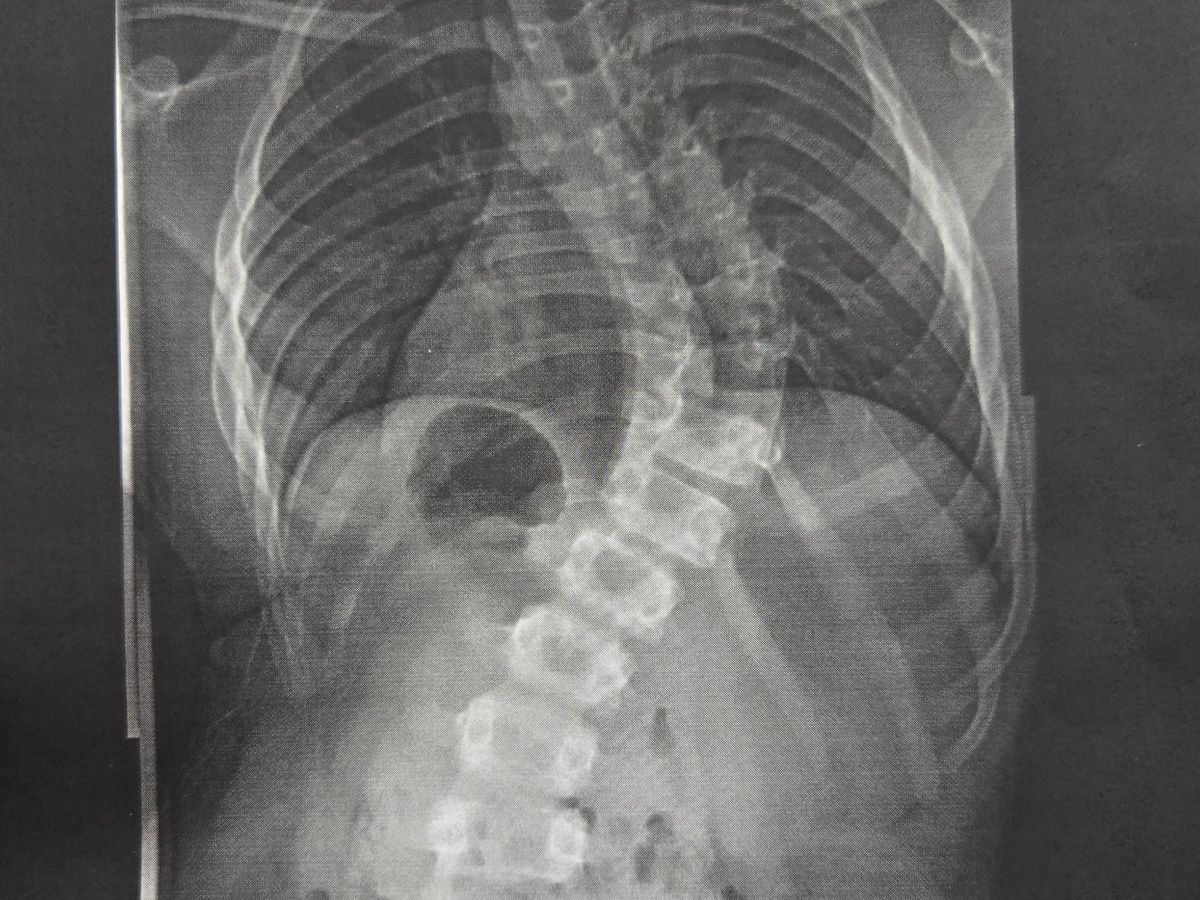

Our youngest son, Ian, has been diagnosed with severe scoliosis and is requiring a major spinal surgery due to his continuous back pain. He is a wonderful and active 12-year-old that has been dealt a crappy hand, but we—his family—are his backup. He has worn a sleeping back brace since January; however, this did not improve his pain level or slow down the curvature. So he now has a 70° curve, but he was only at a 47° curve at the beginning of the year. He has now been prescribed a daytime brace to give him a little relief at school, but that still will not take his pain away. We have been working with his school to accommodate him wherever possible, but his pain has caused him to miss a number of days from school. So now, homebound care is the next step until his surgery and recovery is complete, so that he doesn't fall behind in his schoolwork.